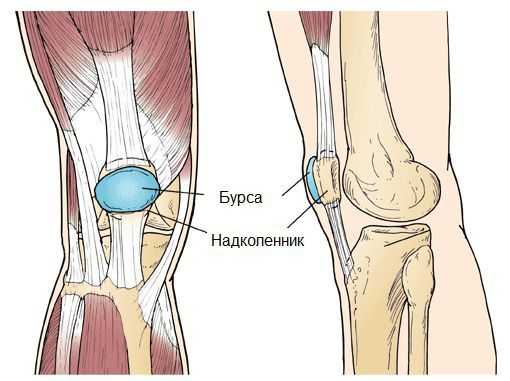

(Слева) Нормальная анатомия коленного сустава, вид сбоку. Бурса очень невелика и располагается между надколенником и кожей. (Справа) При препателлярном бурсите бурса становится воспаленной и отечной.

Рис 1. (Слева) Боковая проекция нормального состояния коленного сустава, при котором бурса, расположенная на надколеннике, имеет незначительные размеры. (Справа) При наличии воспаления бурса отекает и становится крупнее.